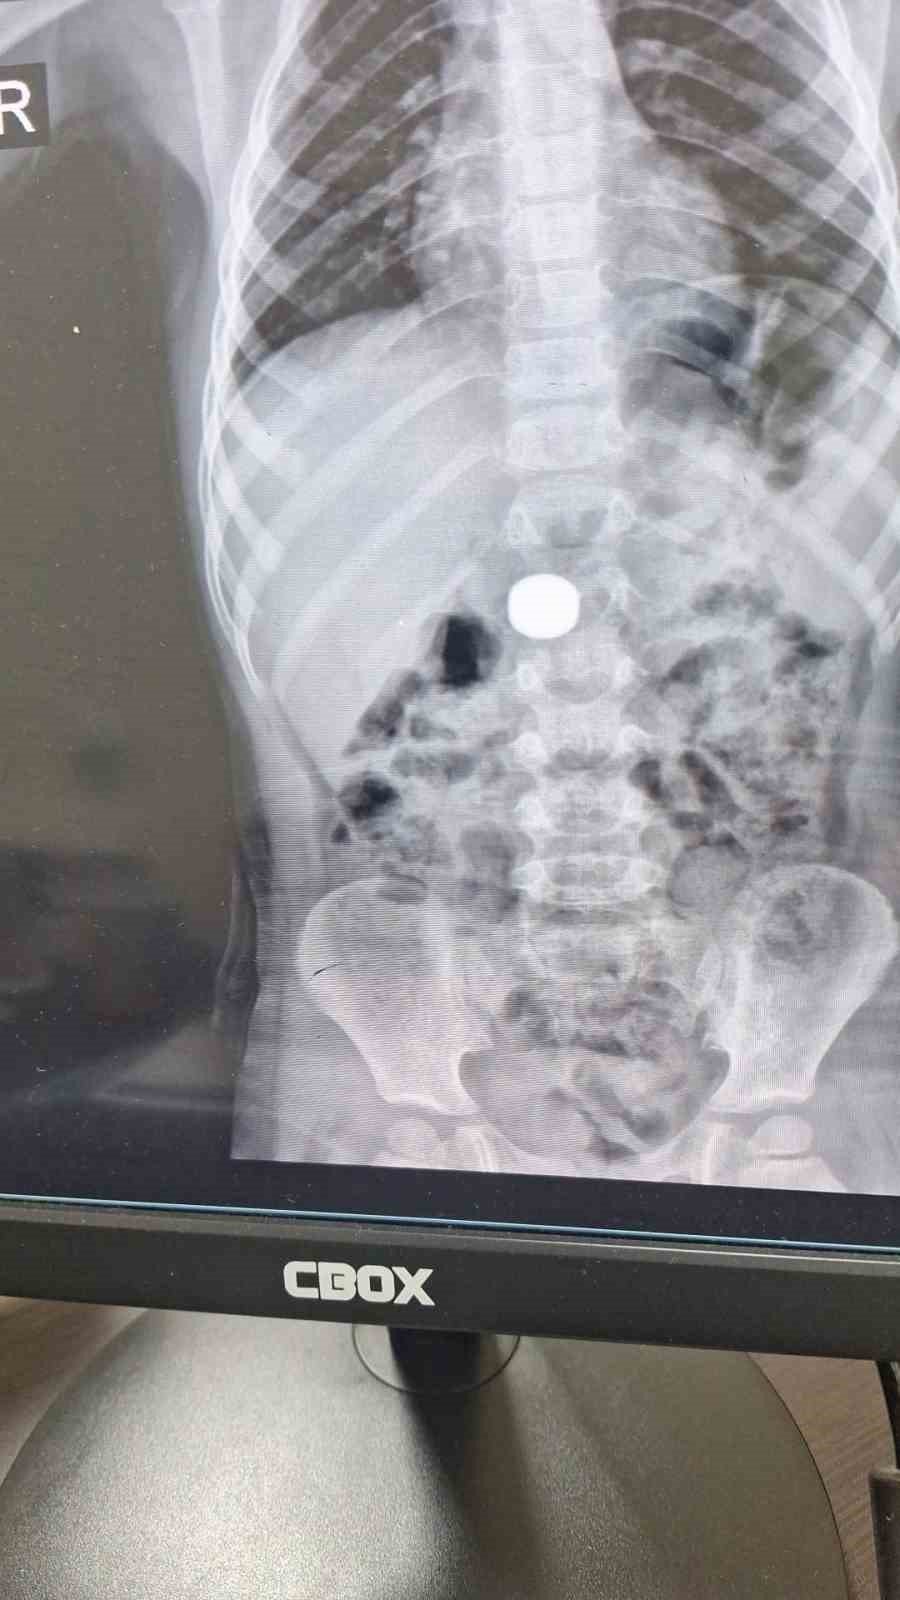

Karaman'da 4 yaşındaki İ.K.'nin mıknatıs yuttuğundan şüphelenen ailesi, Karaman Eğitim ve Araştırma Hastanesi Acil Servisi'ne başvurdu. Yapılan tetkiklerde çocuğun ince bağırsağında iki adet mıknatıs bulunduğu tespit edildi. Gözlem altına alınan çocuğun sağlık durumu 5 gün boyunca takip edildi. Çocuk Cerrahisi Uzmanı Doç. Dr. Mehmet Uysal'ın gerçekleştirdiği operasyonla bağırsakta tıkanıklığa yol açan iki mıknatıs başarılı bir şekilde çıkarıldı.

Hastayı 5 gün boyunca takibe aldıklarını belirten Doç. Dr. Mehmet Uysal, gözetim süresince çekilen filmlerde mıknatısların yer değiştirmediğini söyledi. Uysal, "Hastayı genel anestezi altında ameliyata aldık. İnce bağırsakta iki mıknatısın birbirine yapışık halde olduğunu gördük. Gerçekleştirdiğimiz operasyonla mıknatısları çıkardık. Ameliyat sonrası hastamız üçüncü gününde taburcu edildi. Şu an genel durumu iyi" dedi.